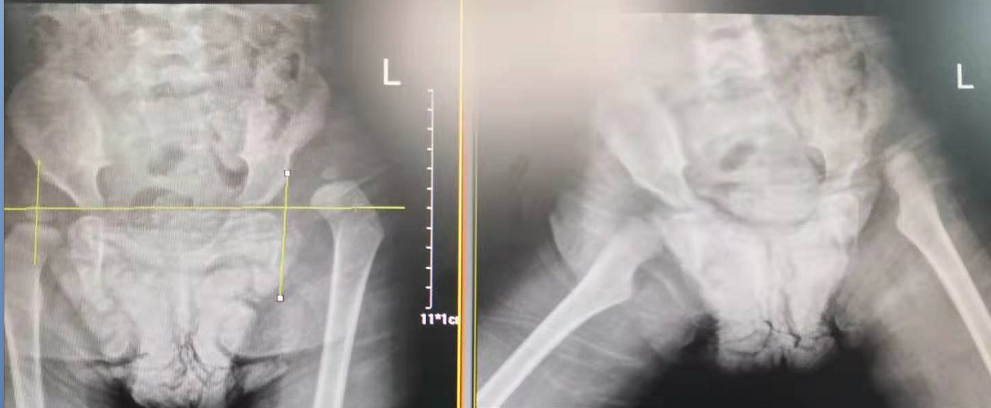

2歲零1個(gè)月的幼兒玥玥(化名)因先天性髖關(guān)節(jié)脫位(也就是我們常說(shuō)的“長(zhǎng)短腿”)來(lái)到了瀘州市中醫(yī)院治療。在醫(yī)院骨傷三科岐黃名中醫(yī)、副主任中醫(yī)師鄭磊的帶領(lǐng)下,科室與麻醉科密切配合,順利為玥玥實(shí)施了手術(shù)。

術(shù)前

術(shù)后

據(jù)了解,玥玥的左腿比右腿要短3厘米,導(dǎo)致她走起路來(lái)“不對(duì)頭”:一拐一拐的,像小鴨子走路一樣。

她的管床醫(yī)生,骨傷三科主治中醫(yī)師茶曉鋒介紹,髖關(guān)節(jié)是由一個(gè)球形股骨頭與倒置球形的髖臼組成的杵臼關(guān)節(jié)。如果髖關(guān)節(jié)發(fā)育不良,可能就會(huì)產(chǎn)生半髖關(guān)節(jié)脫位或者關(guān)節(jié)脫位,從外觀上來(lái)看即形成了大家常說(shuō)的長(zhǎng)短腿、瘸腿、跛行。隨著年齡的增長(zhǎng)及骨骼的發(fā)育,如果沒(méi)有及時(shí)糾正,還將會(huì)造成患者患髖和腰部疼痛。